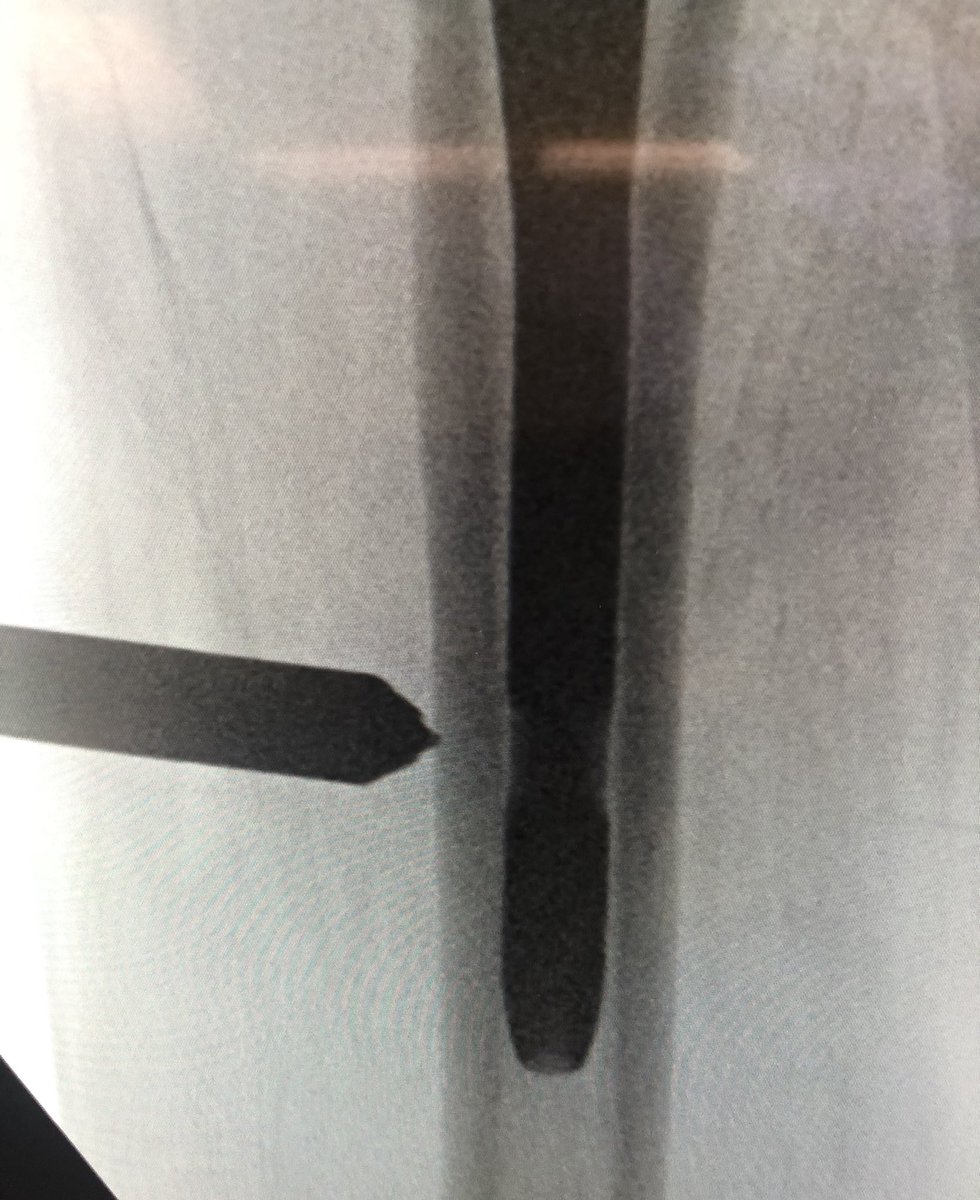

[7/18] Once I’m happy with direction, I switch to driver, drive guidewire in metaphysis, then stop and gently tap again. I look for the guidewire to “bounce” off the medial cortex, ensuring it is in bone (not in fracture) and obviating having to go back to the lateral to check.